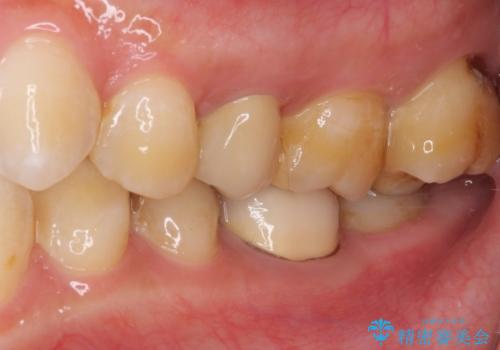

- 冷たいものがしみるとのことで来院された患者様です。

診査を行った結果、第一小臼歯にある樹脂の詰め物(コンポジットレジン)と歯の境目が痛みの原因であることが分かりました。

また、隣接する第二小臼歯も虫歯になっていることも分かったため、2歯を同時に治療するにしました。

下顎の目立つ位置であるため、セラミックインレーによる修復治療を行うこととしました。

精密に型取りを行ったセラミックインレーを装着したことで、治療後にはしみたり痛んだりという症状は治まりました。